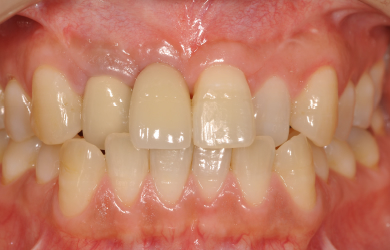

| 治療内容 | インプラント1本(GBR+自家骨移植)、メタルボンドセラミック2本 | ||||||||||||||||||||||||||||||||

| 治療期間 | 6ヶ月 |